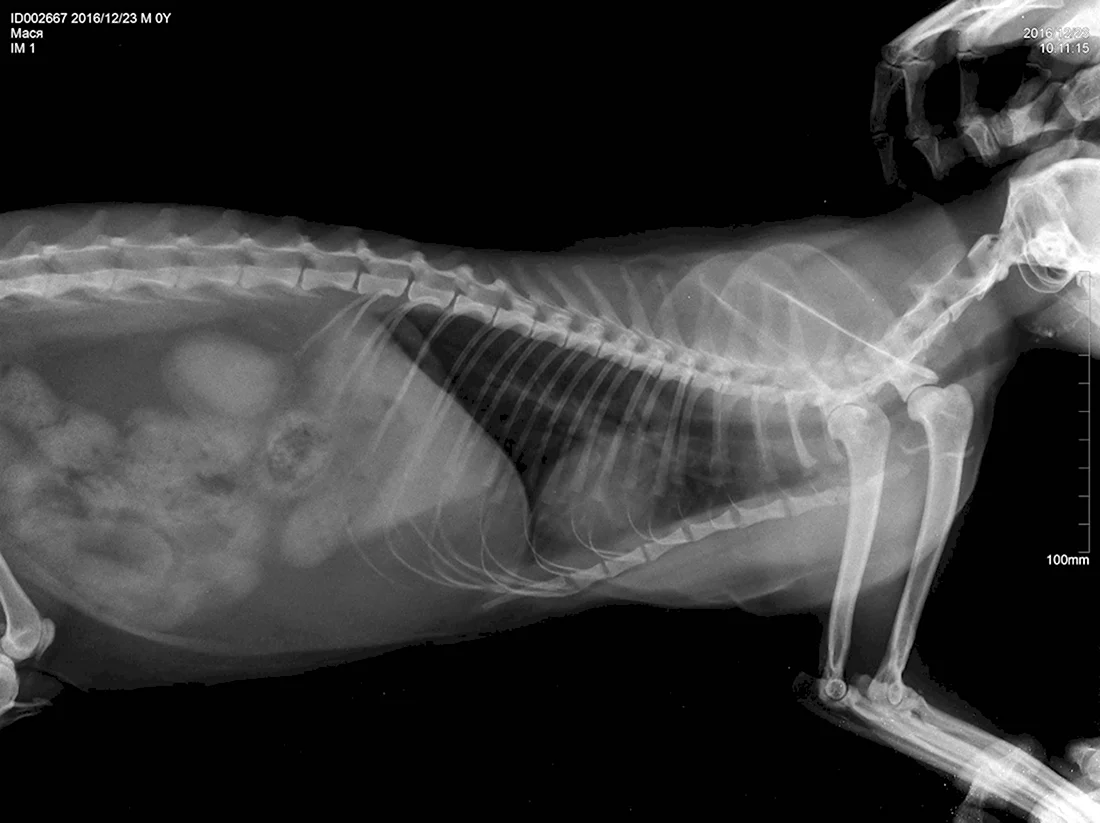

В данной статье представлена уникальная галерея фотографий, которые запечатлевают нежное чудо жизни — котят в утробе кошки. Вас ждут 35 потрясающих фото и картинок, позволяющих заглянуть в мир развивающихся маленьких созданий. Приглашаем вас окунуться в эту удивительную галерею и насладиться прекрасными видами эмбрионов кошачьих детенышей.

Так трогательно и волнующе наблюдать за процессом формирования новой жизни внутри мамы-кошки на этих удивительных фотографиях.